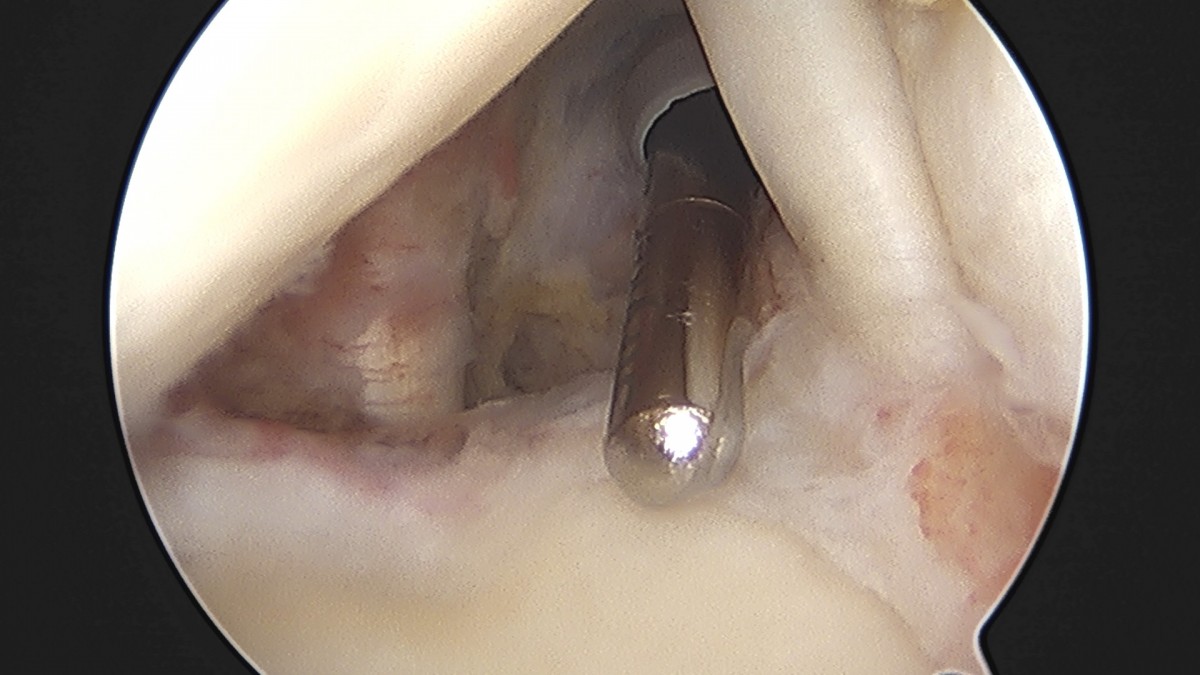

이재상원장님 어깨 견봉하 감압술 및 관절낭 이완술 음성O 환자

작성자 최고관리자 댓글 0건 조회 805회 작성일 25-09-16 15:32